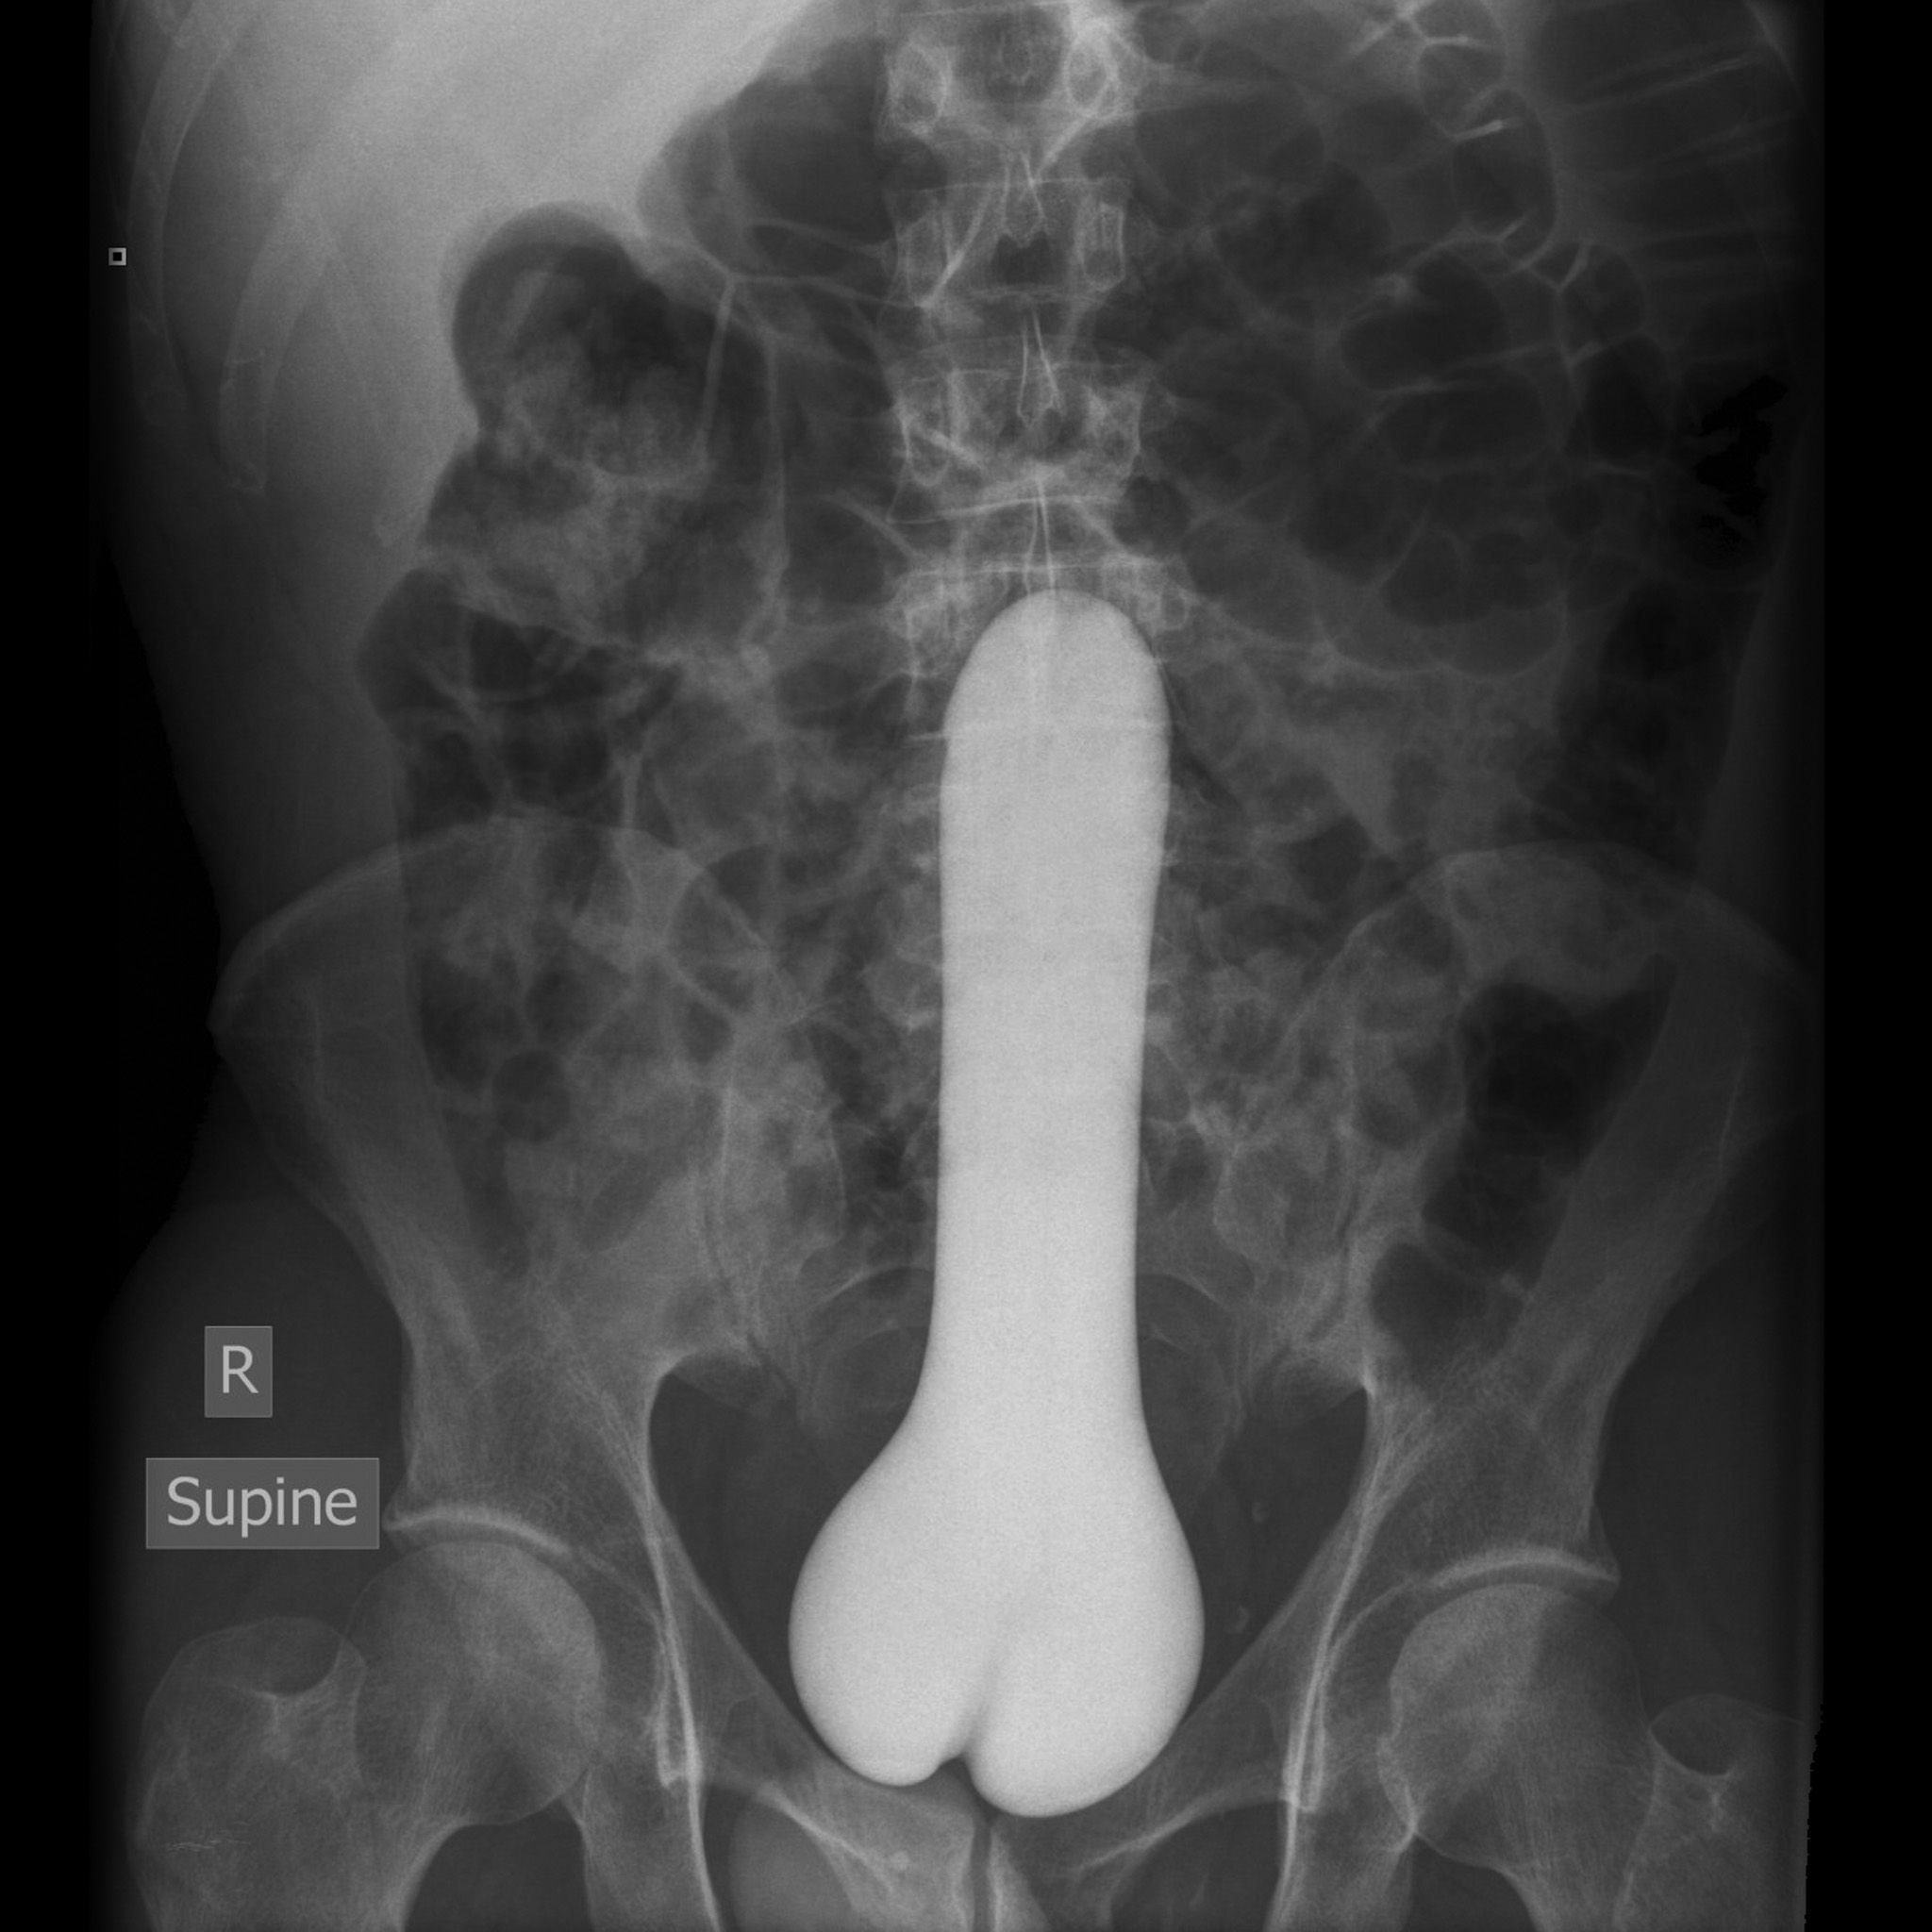

Удивительные рентгенограммы: инородные предметы в человеческом теле